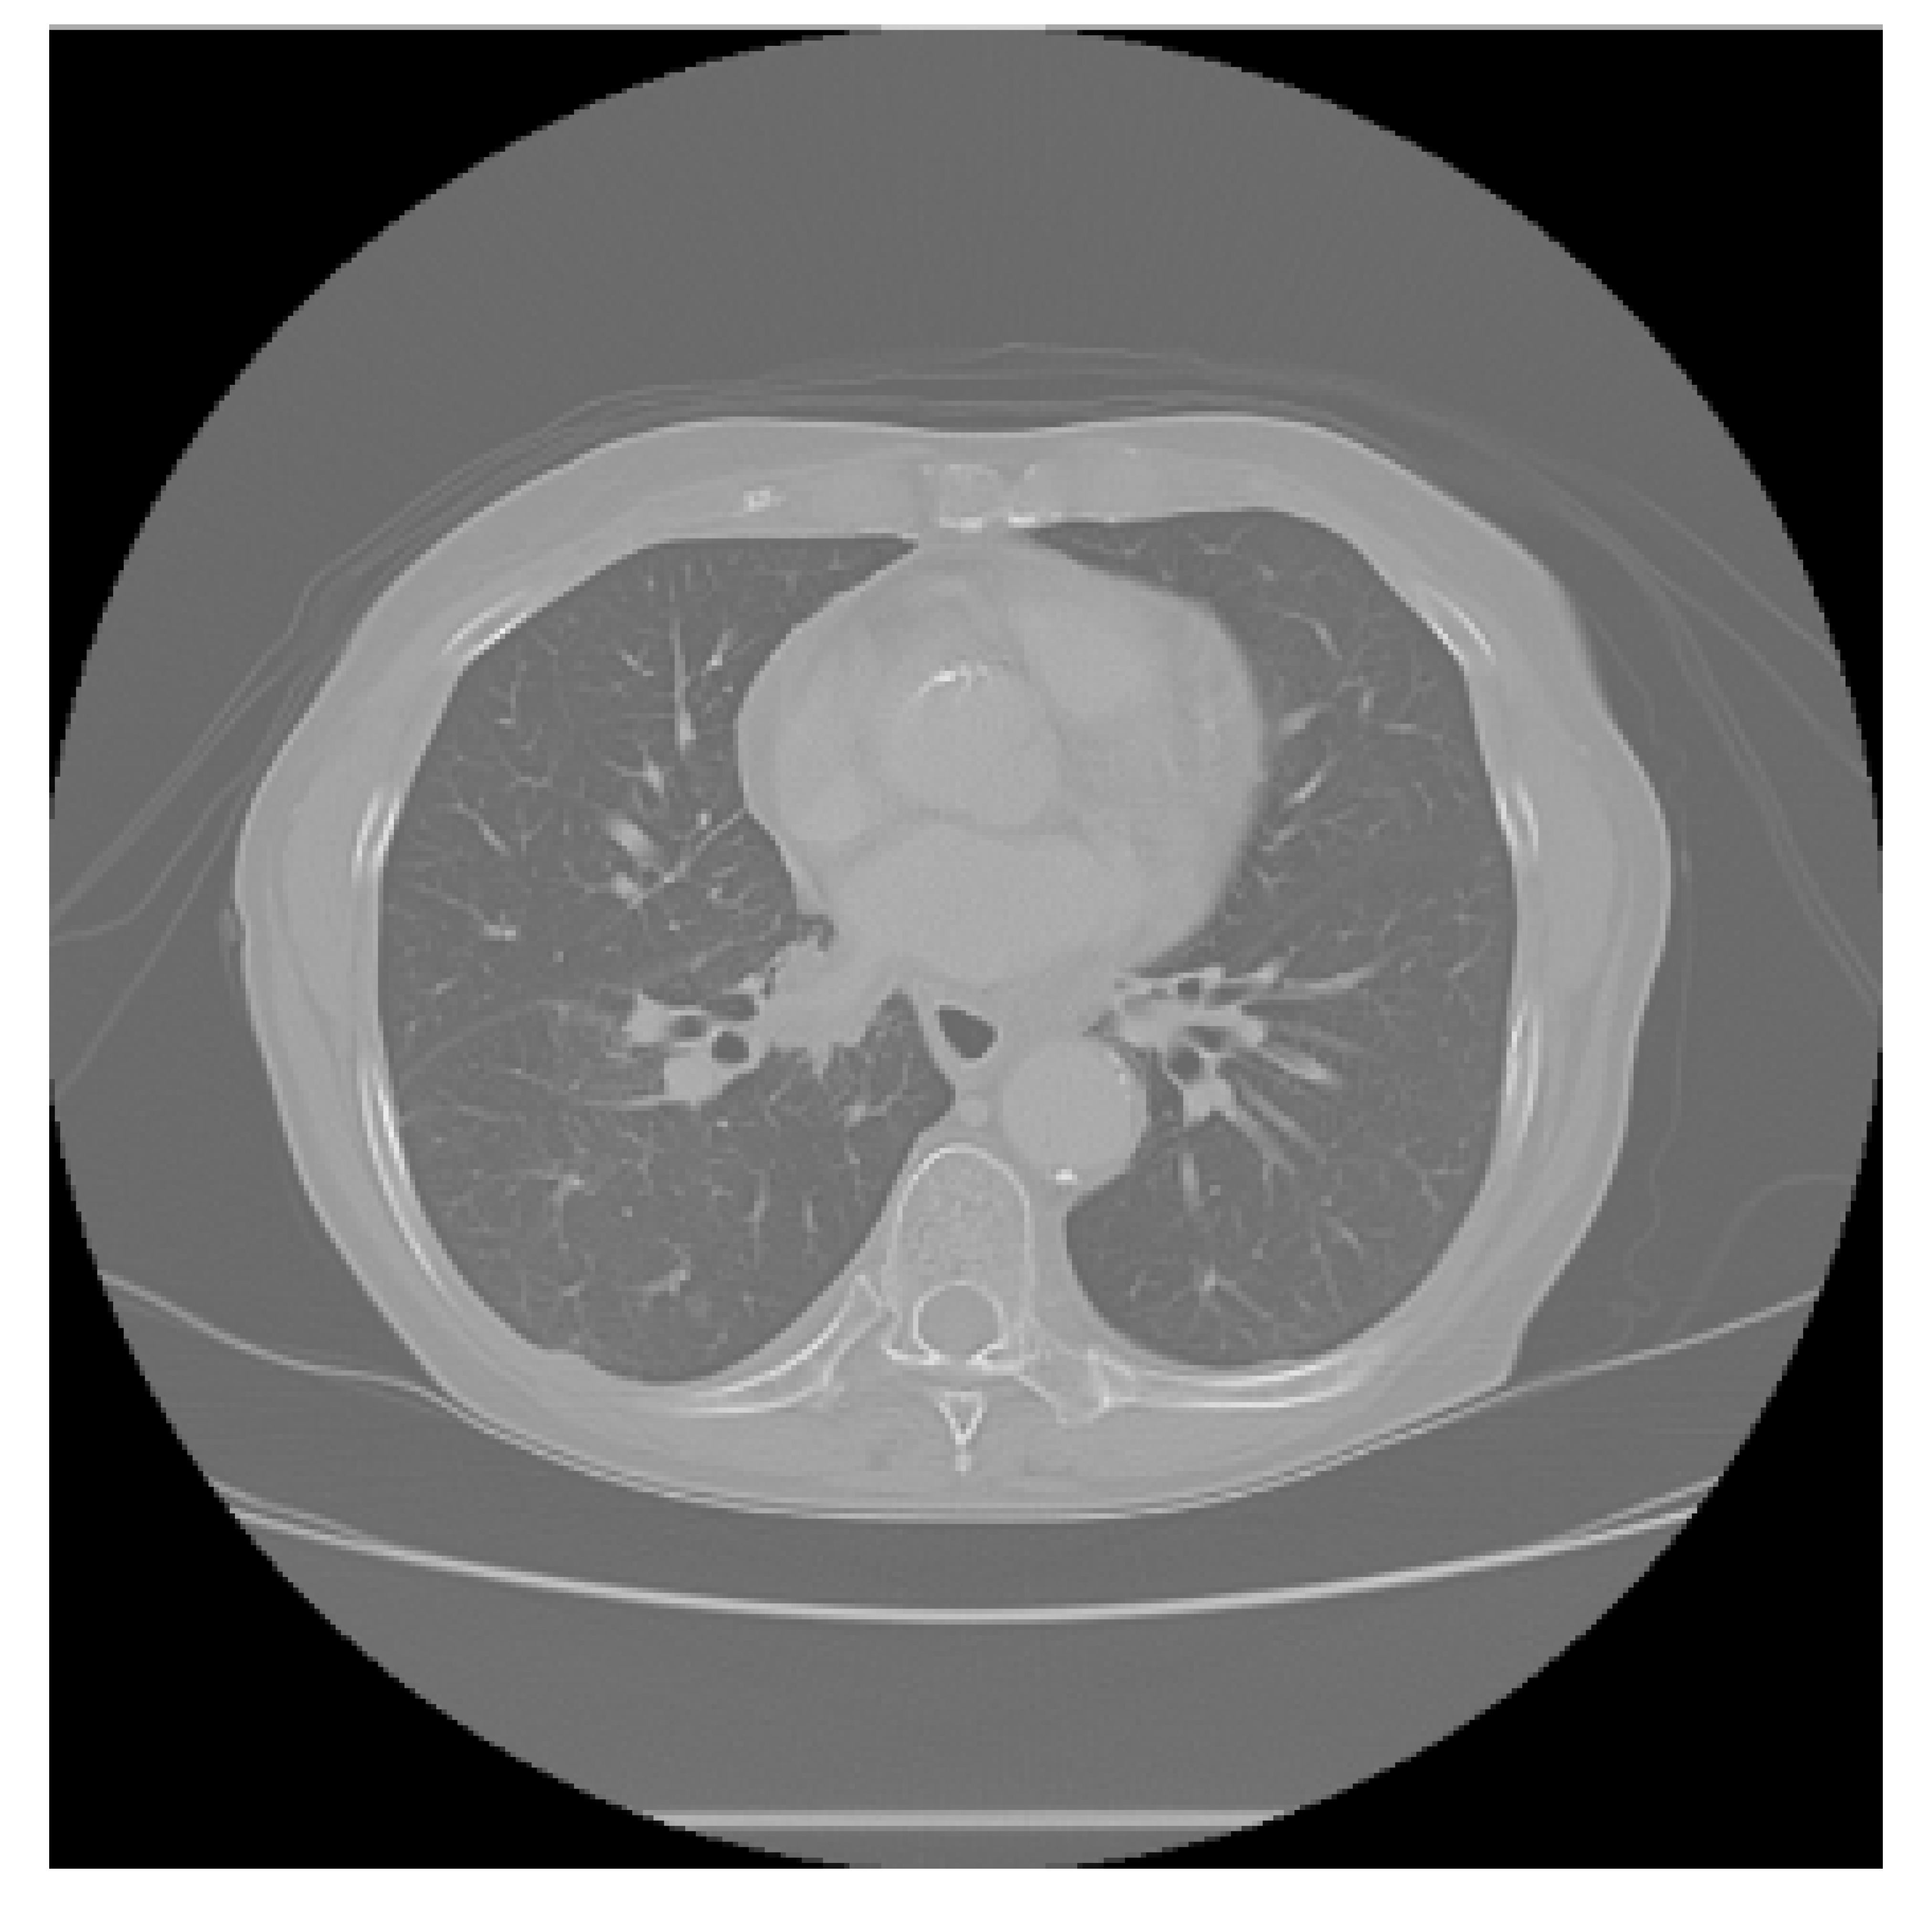

The APILungCancer interface provides intuitive functionality for loading and analyzing DICOM medical images. In the Load DICOM Images section, users can select and process CT scans for lung cancer evaluation. Once an image is loaded and analysis is performed, the software presents a visualization of the image along with the predicted probability of cancer (Table 7). Our study focused on lung cancer, including subtypes such as adenocarcinoma, squamous cell carcinoma, and small cell carcinoma. About 1000 training images and 300 test images from the CMB-LCA dataset were used to develop and validate the system.

In this example (Figure 5), the DICOM image 1-27.dcm from the test set was processed and the software calculated a cancer probability of 0.4267 (42.67%), indicating a high likelihood of malignancy.

Figure 5.

Determination of the probability of lung cancer. Example output of the system for the image 1-27.dcm, yielding a predicted probability of 42.67%, consistent with Table 7.

This value matches the result in Table 7, confirming the consistency of the predictions generated by the AI-based model integrated into the system.